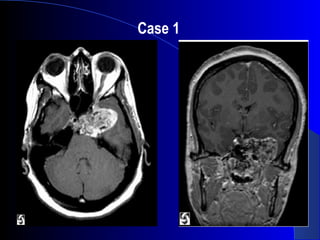

Case 2

CT/MRI Findings:

• Expansile lytic lesion, midline

• Well delineated mass arising from bone

• Large soft tissue component

• Variable calcification

• Anteroposterior extension

• Heterogeneous enhancement on T1, T2

• Dark on T1, bright on T2

Chordoma

Differential Diagnosis:

• Chondroma

• Chondrosarcoma

• Clivus meningioma

Origin

• Notochord remnants

Location

• Clivus 35%

• Sacrum 50%, Vertebral bodies 15%

Clinical

• age 30-70

• Slow growing, locally aggressive

• CN VI- CN deficits

• Mets late

• Tx: surgery, radiation

• #56 Sagittal T1-weighted MR image shows a large, hypointense soft-tissue mass that arises from the distal clivus with anterior extension into the nasopharynx (arrows) and extradural extension into the posterior fossa (arrowhead).

• #57 CT to assess degree of bone involvement. MRI to evaluate extension of tumor. CT Findings: The most characteristic appearance of intracranial chordoma is of a centrally located homogeneous soft tissue mass arising from the clivus and causing adjacent bone destruction. Calcification is common but variable. Areas of low attenuation within the soft tissue mass occasionally are found on CT, representing the myxoid and gelatinous material found on pathologic examination. CT reliably demonstrates petrous apex involvement and lysis of the skull base foramina. MRI Findings: Mass originating from midline with extension primarily in the anteroposterior axis rather than laterally. Well delineated. Expands bone in the early stage = indicator that it arises from bone, not from adjacent structures. Post gad = lobulated area, heterogeneous on T1 and T2 b/c of mucinous and gelatinous contents. DDX: Chondroma- similar appearance but extend more laterally into sellar and cerebellopontine angles. Clivus meningioma – homegeneous signal, dural attachment

• #58 Contrast enhanced T1 spin echo image. Chordoma of the upper part of the clivus with posterior extension into the pontine cistern. Chordomas = benign tumor but has significant problems b/c of location, local invasion, recurrence. Origin: Notochord = early fetal axial skeleton. Gets surrounded by cartilage. Cartilage ossifies and notochord = squeezed out into intervertebral regions = nucleus pulposus of intervertebral disks. Can get remnants then, along any position of the neural axis- turn into chordomas. Location: read slide. Rare. &amp;lt;0.2% of all intracranial tumors. Clinical:read slide CN deficits: HA, dysphagia, facial pain, facial paresis, visual loss, hearing loss, and ataxia. CT to assess degree of bone involvement. MRI to evaluate extension of tumor. CT Findings: The most characteristic appearance of intracranial chordoma is of a centrally located homogeneous soft tissue mass arising from the clivus and causing adjacent bone destruction. Calcification is common but variable. Areas of low attenuation within the soft tissue mass occasionally are found on CT, representing the myxoid and gelatinous material found on pathologic examination. CT reliably demonstrates petrous apex involvement and lysis of the skull base foramina. MRI Findings: Mass originating from midline with extension primarily in the anteroposterior axis rather than laterally. Well delineated. Expands bone in the early stage = indicator that it arises from bone, not from adjacent structures. Post gad = lobulated area, heterogeneous on T1 and T2 b/c of mucinous and gelatinous contents.